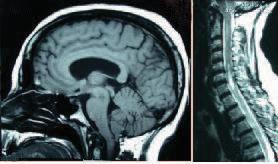

颅颈交界区畸形(Chiari Ⅰ型和脊髓空洞症:分类、诊断和治疗)。

Malformations of the craniocervical junction (Chiari type I and syringomyelia: classification, diagnosis and treatment).

Chiari disease (or malformation) is in general a congenital condition characterized by an anatomic defect of the base of the skull, in which the cerebellum and brain stem herniate through the foramen magnum into the cervical spinal canal. The onset of Chiari syndrome symptoms usually occurs in the second or third decade (age 25 to 45 years). Symptoms may vary between periods of exacerbation and remission. The diagnosis of Chiari type I malformation in patients with or without symptoms is established with neuroimaging techniques. The most effective therapy for patients with Chiari type I malformation/syringomyelia is surgical decompression of the foramen magnum, however there are non-surgical therapy to relieve neuropathic pain: either pharmacological and non-pharmacological. Pharmacological therapy use drugs that act on different components of pain. Non-pharmacological therapies are primarily based on spinal or peripheral electrical stimulation. It is important to determine the needs of the patients in terms of health-care, social, educational, occupational, and relationship issues, in addition to those derived from information aspects, particularly at onset of symptoms. Currently, there is no consensus among the specialists regarding the etiology of the disease or how to approach, monitor, follow-up, and treat the condition. It is necessary that the physicians involved in the care of people with this condition comprehensively approach the management and follow-up of the patients, and that they organize interdisciplinary teams including all the professionals that can help to increase the quality of life of patients.

Chiari 病(或畸形)通常是一种先天性疾病,其特征是颅底解剖缺陷,小脑和脑干通过枕骨大孔疝入颈椎椎管。Chiari 综合征症状的发作通常发生在第二或第三个十年(25 至 45 岁)。症状在加重和缓解期之间可能会有所不同。对于有或无症状的患者,神经影像学技术可用于诊断 Chiari Ⅰ型畸形。对于 Chiari Ⅰ型畸形/脊髓空洞症患者,最有效的治疗方法是枕骨大孔减压术,但也有非手术治疗方法来缓解神经病理性疼痛:药物和非药物。药物治疗使用作用于疼痛不同成分的药物。非药物治疗主要基于脊髓或外周电刺激。除了与信息相关的方面,重要的是要确定患者在医疗保健、社会、教育、职业和人际关系问题方面的需求,特别是在症状出现时。目前,专家们对于该疾病的病因或如何进行治疗、监测、随访和治疗该病尚无共识。参与此类疾病患者护理的医生必须全面处理患者的管理和随访,并组织包括所有能够帮助提高患者生活质量的专业人员在内的跨学科团队。